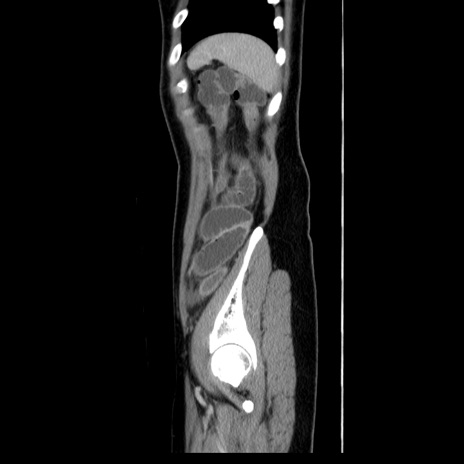

CT